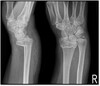

Q

What are the signs that a distal radius fracture is present?

A

Trabecular pattern, lucency, slight posterior angulation and cortical disruption anteriorly